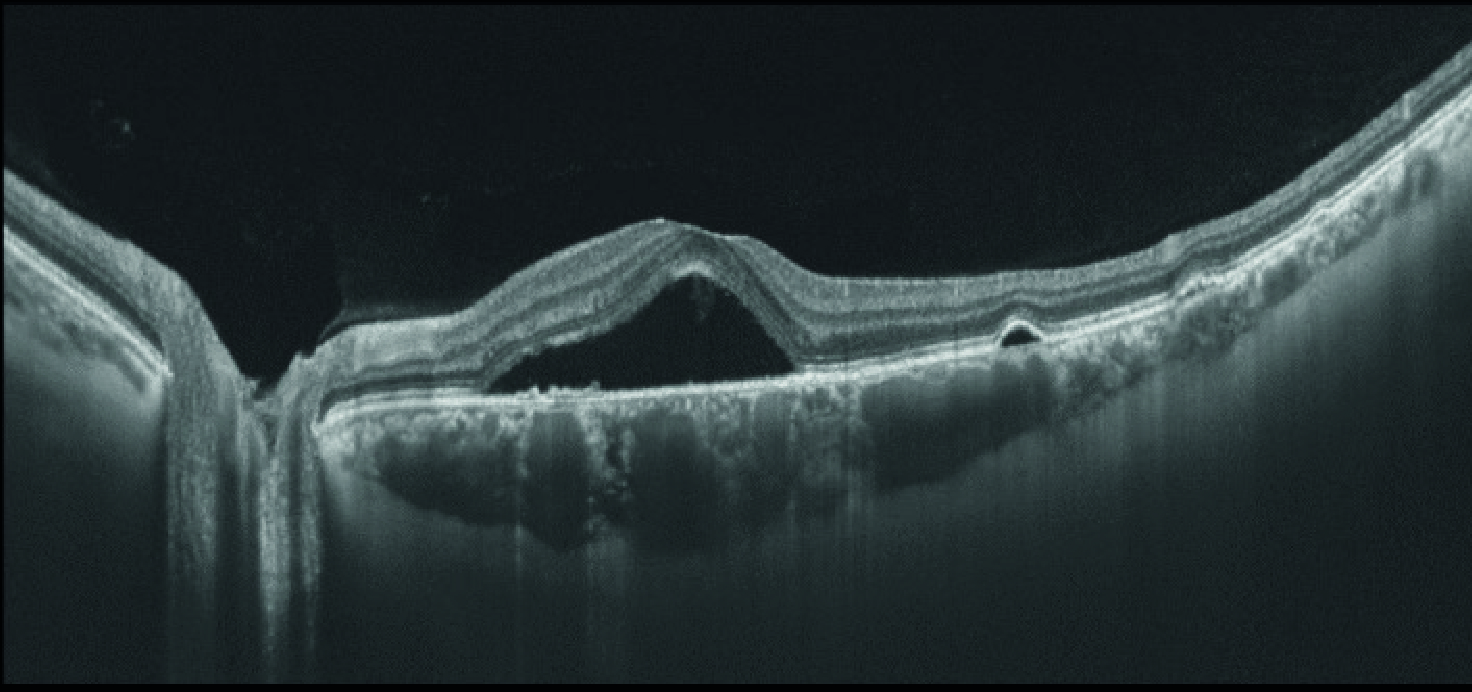

Визуализация высокого разрешения на ОКТ с перестраиваемым лазерным источником света

Глубокое сканирование с высоким разрешением